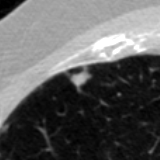

The current study focuses on lung nodule retrieval from a database of CT scans, where patches taken from CT slices of pulmonary nodules are to be mapped into an embedding. LIDC-IDRI [5] is a dataset of thoracic CT scans of 1,010 patients. All the scans were annotated by up to four radiologists, where each one identified, segmented and evaluated separately the lung nodules of a diameter above . Their evaluation also included ratings for a set of 9 characteristics: Subtlety, Internal structure, Calcification, Sphericity, Margin, Lobulation, Spiculation, Texture and Malignancy. The rating system was based on a discrete score of 1-5. Four examples of nodule patches are illustrated in Figure 2: 2 benign (a, b) and 2 malignant (c, d). A rounded vector of the mean rating is bellow each nodule, with the characteristics ordered according to the listing above. The most prominent difference between a and b is the calcification: 3 (solid) and 6 (absent) accordingly. d compared to c has a more defined margin, is more lobulated, but less spiculated. The malignancy score is used to define malignancy classes: score of 1-2 is benign, score of 3 is unknown, and a score of 4-5 is malignant.

(a) Benign

3, 1, 3, 3, 4, 3, 1, 5, 1

(b) Benign

3, 1, 6, 5, 5, 1, 1, 5, 2

(c) Malignant

5, 1, 6, 3, 3, 4, 1, 5, 5

(d) Malignant

4, 1, 6, 3, 4, 2, 2, 5, 4